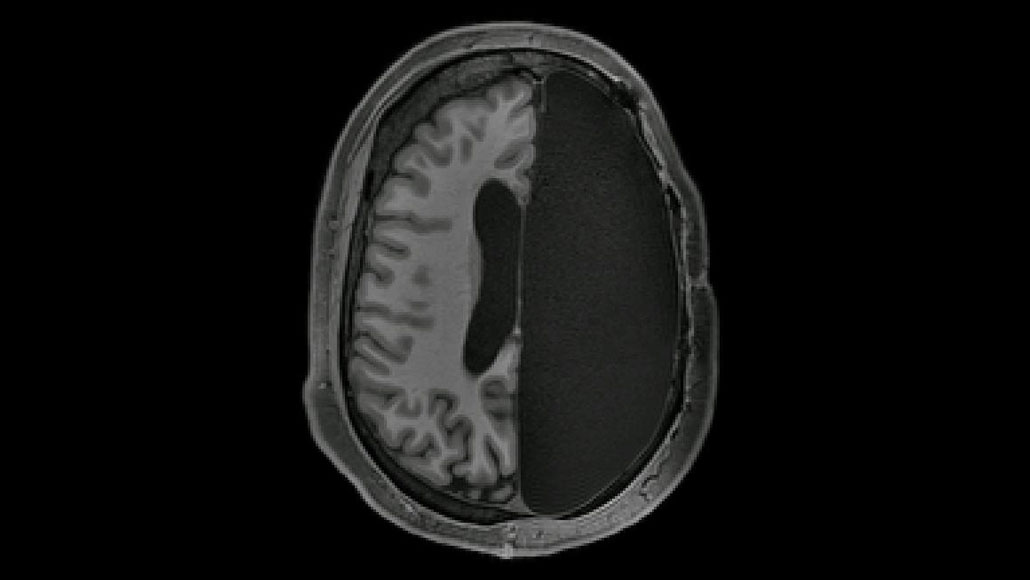

Despite having only half of a brain, certain neural connections appear to be stronger than those in a fully intact brain, a new study suggests.

A detailed study of six adults who, as children, had half of their brain removed to treat severe epilepsy, shows how brains can reorganize and bounce back. As extreme as the surgery is, many of these people keep or recover language and thinking skills. In a new study, researchers from Caltech and their colleagues discovered one way the brain might compensate.

While the six participants rested in an MRI scanner, researchers measured blood flow in seven brain regions that handle jobs such as vision, attention and movement. In the experiment, blood flow served as a proxy for brain activity. When activity in one part of the brain changes in lockstep with activity in another, that implies that the regions are working together and sharing information. These are signs of strong connections, which are thought to be crucial for a healthy brain.

In the six people who had had hemispherectomies, these seven brain systems seemed to be working normally. In fact, the connections between those seven systems were even stronger than such connections in six people with whole brains, the researchers report November 19 in Cell Reports. Such stronger-than-normal connections might help explain how these post-surgery brains compensate for missing parts, the researchers suspect.